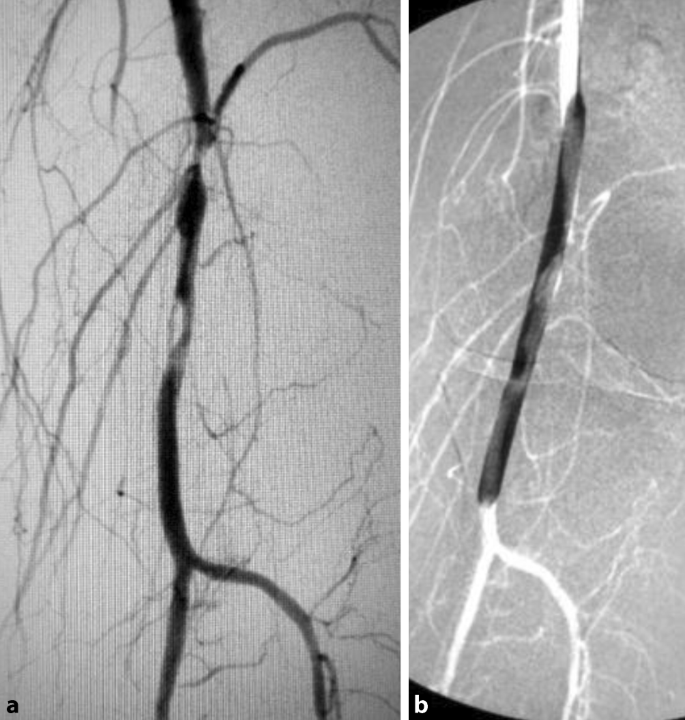

Diabetisches Fußsyndrom – Teil 2 | SpringerLink